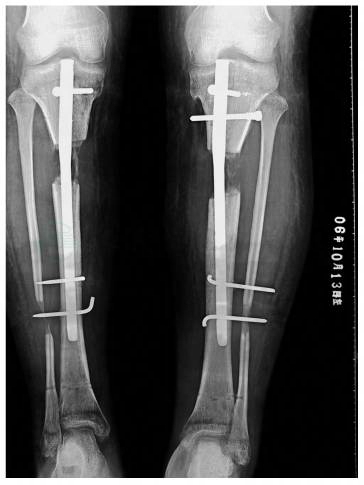

图3 术后X线片

术后7天开始延长双大腿外侧,每次延长1/6圈,每日4次,每次间隔最少3小时,纠正股骨外翻畸形。术后14天,开始延长胫骨,术后3周开始负重练习。延长期间定期测量下肢力线,判断膝内翻矫正程度,并避免下肢旋转。术后1个月,复查X线,双膝内翻畸形纠正,胫骨延长1.2cm,停止延长股骨。术后约4个月,膝关节屈伸活动范围0°~30°,踝关节背伸受限。X线:双侧股骨截骨,骨痂中量,胫骨延长4cm,骨痂少量(图4、图5)。手术去除股骨外固定支架,同时加强下肢功能的锻炼。术后6个月,双膝关节活动范围0°~60°,踝关节背伸左踝5°,右踝0°。X 线:双股骨矫形,骨痂大量,双胫腓骨延长约5cm,截骨面间骨痂中量。手术去除外固定支架,透视下,2枚直径3mm克氏针,由胫骨髓内钉远端锁定孔内侧至外侧固定,折弯针尾,埋于皮下(图6~图8)。